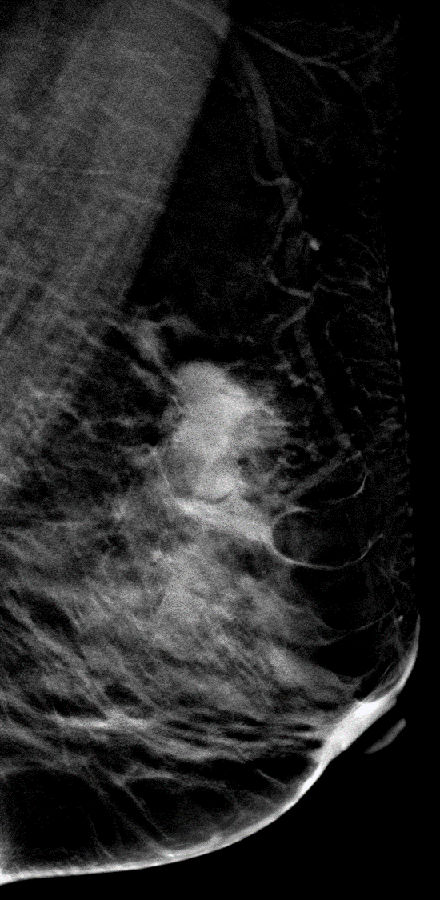

DBT图像:

常规2D和V-Preview图像左乳外上象限可到一不规则形团块影,呈分叶状,肿块的部分界限不清,在DBT图像上我们可以清楚观察到肿块的大小范围及边缘呈细小毛刺样改变。

DBT图像对观察肿块大小、范围及周边情况显示清晰,可以给我们诊断提供了更多影像诊断信息。